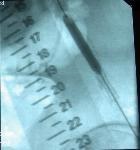

PTA se provádí v místním znecitlivění a je to výkon nebolestivý. Do tepny obvykle v třísle se zavede jehla, přes kterou zavedeme vodič a kterým pronikneme skrz postiženou oblast až do „zdravé“ tepny. Poté do postižené oblasti zavedeme speciální balonkový dilatační katetr (balónek) a „nemocnou“ tepnu ošetříme buď pouze roztažením balonku nebo zavedením stentu, který drží požadovaný průměr ošetřované tepny. Současně se získávají snímky léčené oblasti před a po léčbě pomocí PTA. Na konci výkonu lékař odstraní zaváděcí pouzdro, balonek a vodič (instrumentárium) a místo, kudy bylo instrumentárium zavedeno se stlačí na dobu nezbytně nutnou k zástavě krvácení z tepny. Délka výkonu je zcela individuální v závislosti na lokalizaci a závažnosti postižení tepenného systému. Délku výkonu upřesní výkon provádějící intervenční radiolog.